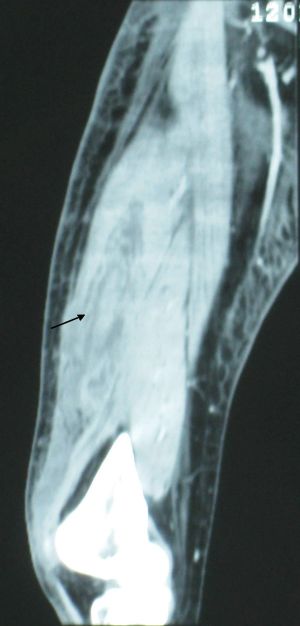

단순 방사선 촬영(X-ray)은 초기 단계에서 괴사성 근막염을 연조직염과 구별하기 어렵다.[15] X-레이는 괴사성 변화를 강력하게 시사하는 피하 기종(피하 조직 내 가스)을 감지할 수 있지만, 공기는 종종 후기 단계에서 나타나며 모든 괴사성 피부 감염이 피하 기종을 생성하는 것은 아니다. 따라서 방사선 촬영은 괴사성 근막염의 초기 진단에 권장되지 않는다.[15] 하지만 이물질이나 골절과 같은 감염원을 식별하여 후속 치료에 도움이 될 수 있다.[15]